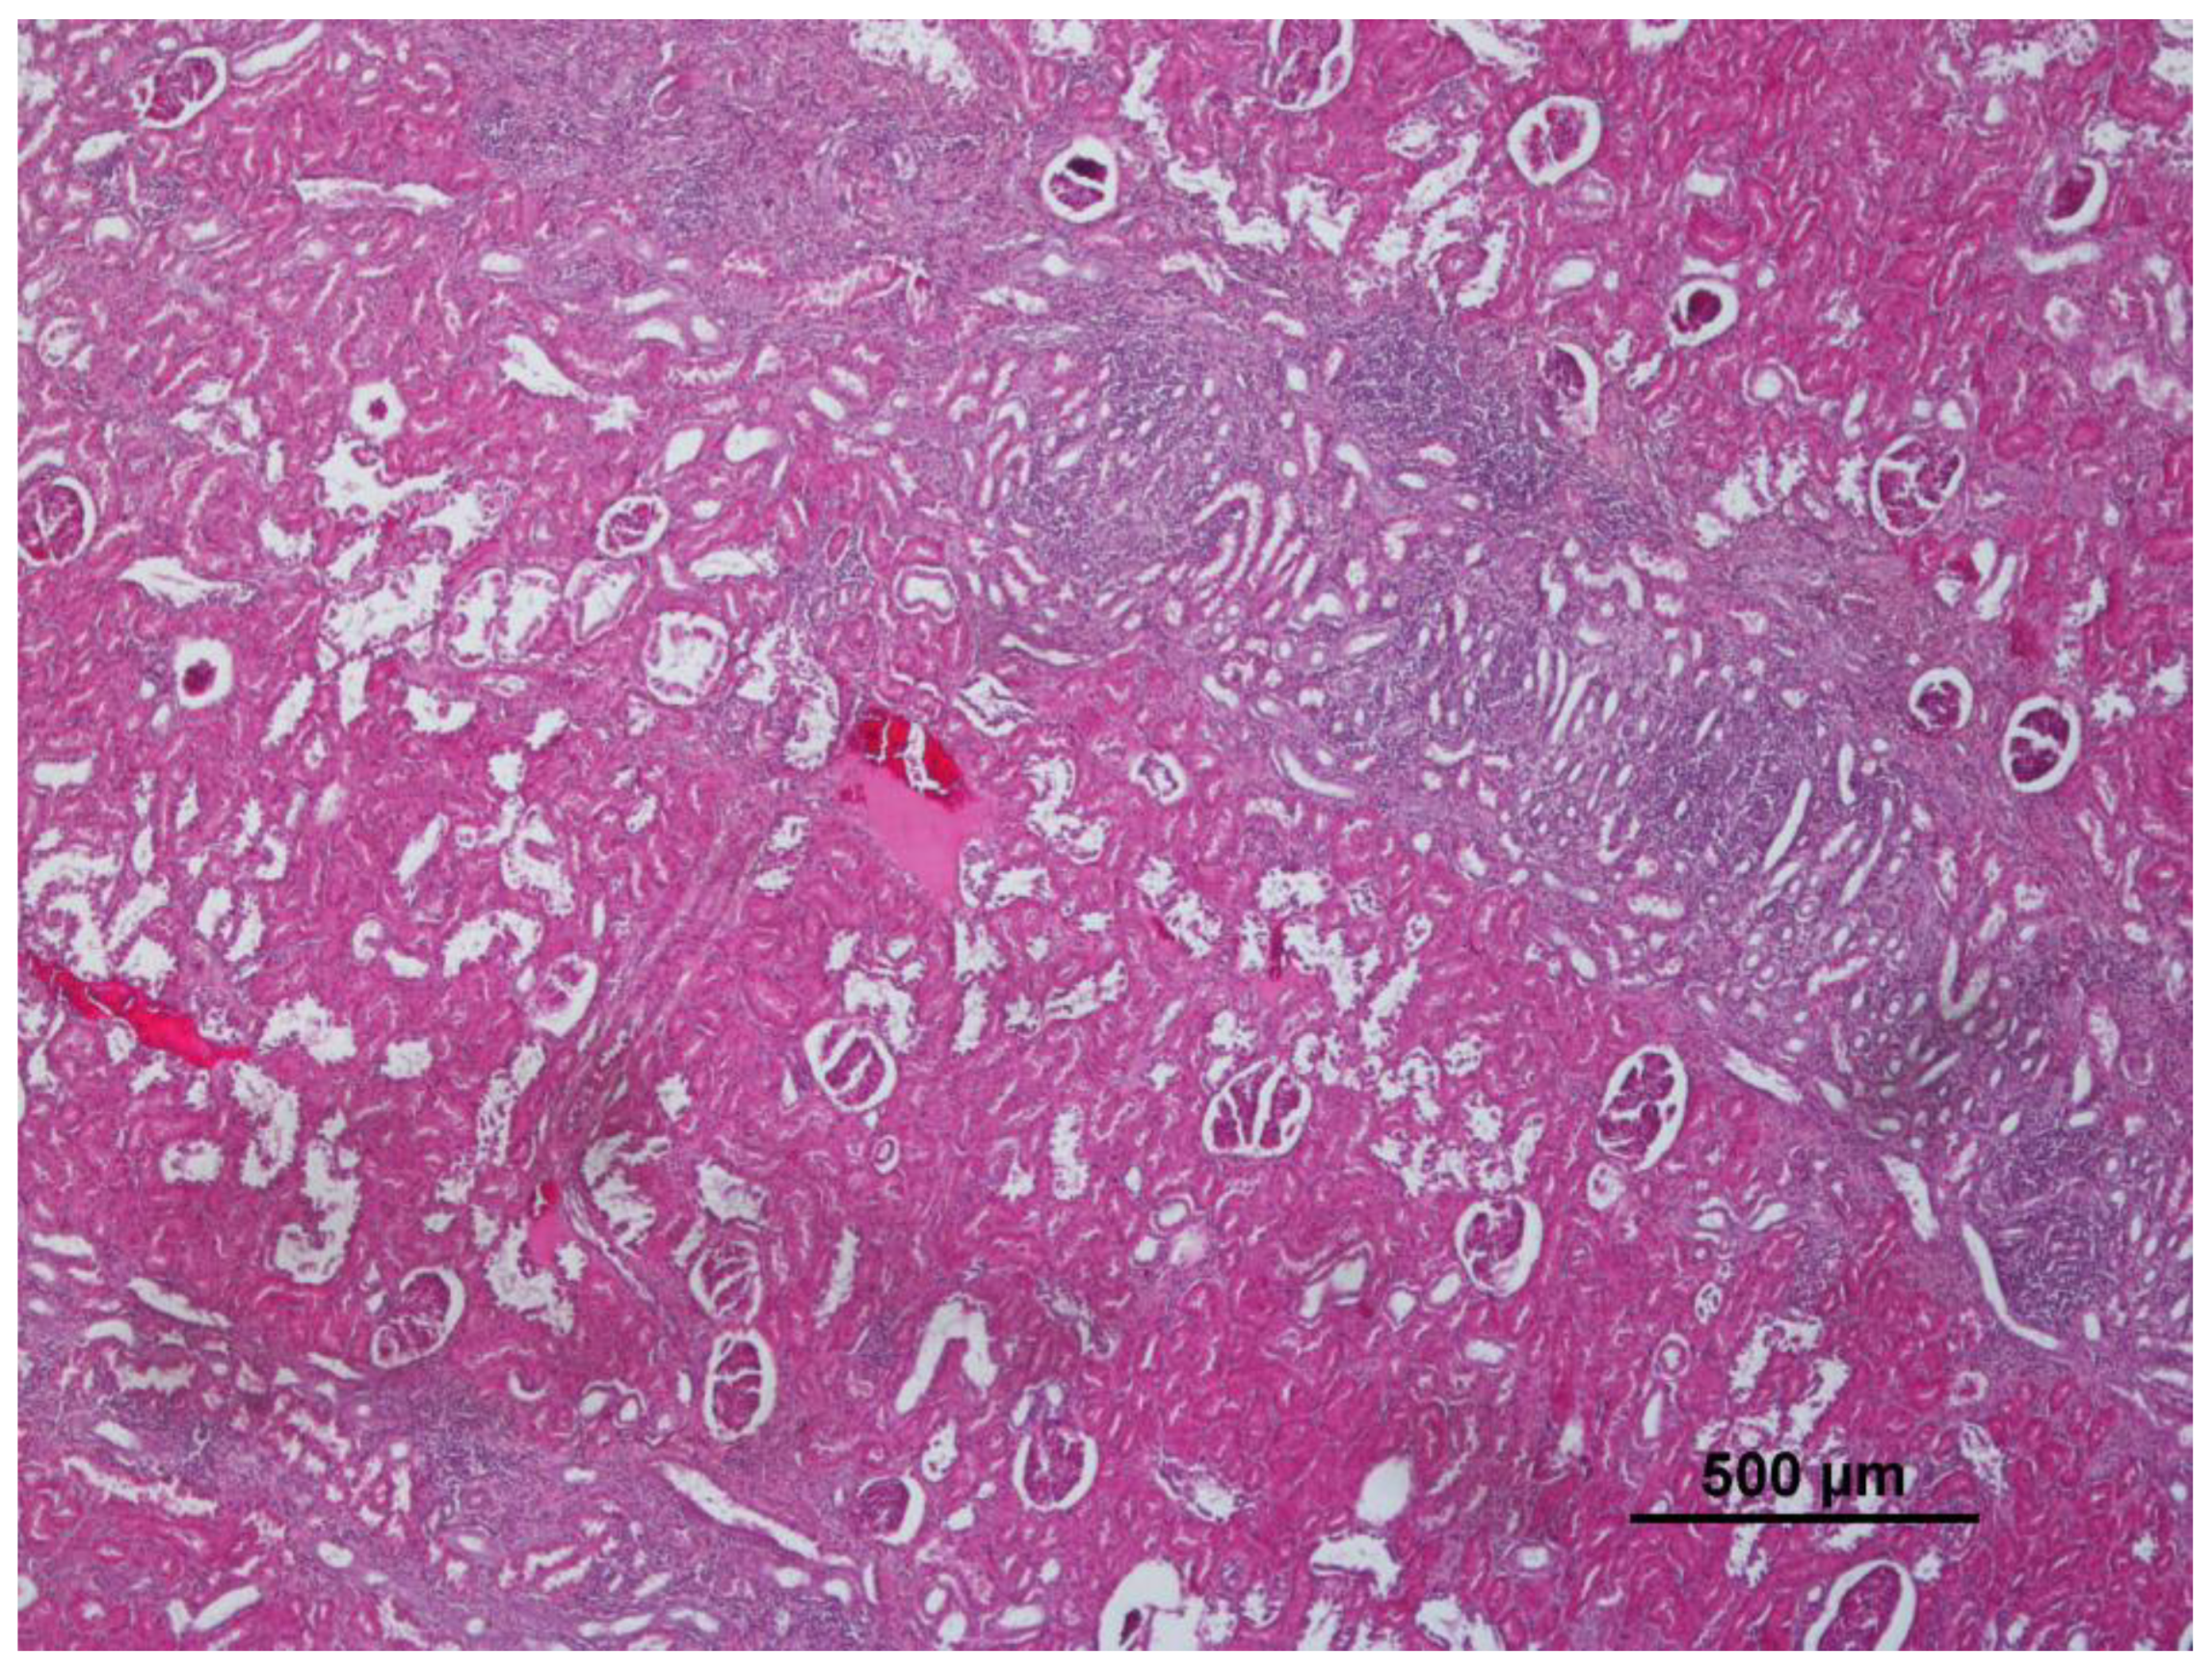

3.1. Lung

| Verminous bronchitis | 25 | 34.7 | panlobular | 8 | 11.1 | Renal steatosis | 2 | 2.8 |

| Lymphoid hyperplasia | 26 | 36.1 | Cellular changes: cell swelling; hydropic change; vacuolar change | 24 | 33.3 | Non-purulent nephritis | 16 | 22.2 |